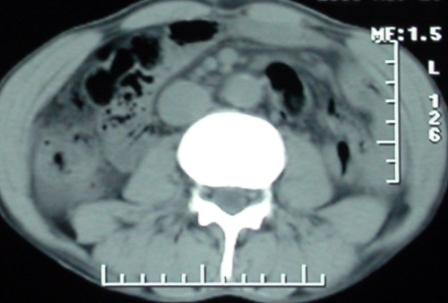

作者: rsyby 时间: 2006-12-6 02:51

手术结果:

肝脏尾状叶肝癌(沿肝十二指肠韧带向下韧带内生长,门腔间隙外压增大),大结节性肝硬化,胆囊积脓,胆道感染。术中见肝外胆道2cm直径,肿瘤向前压迫胆管至扁平状态。